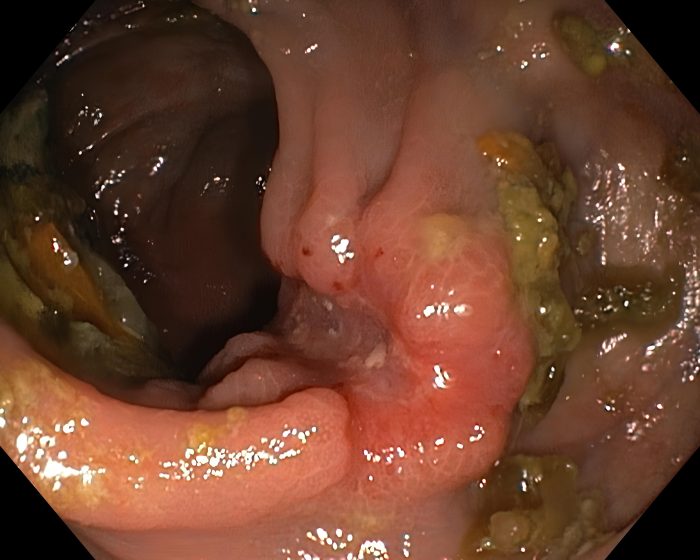

Небольшая блюдцеобразная карцинома восходящей ободочной кишки — типичный пародированный эмбрион

Эндоскопическая картина типичного пародированного эмбриона — эндофитной раковой опухоли с быстрыми темпами роста (восходящий отдел ободочной кишки).